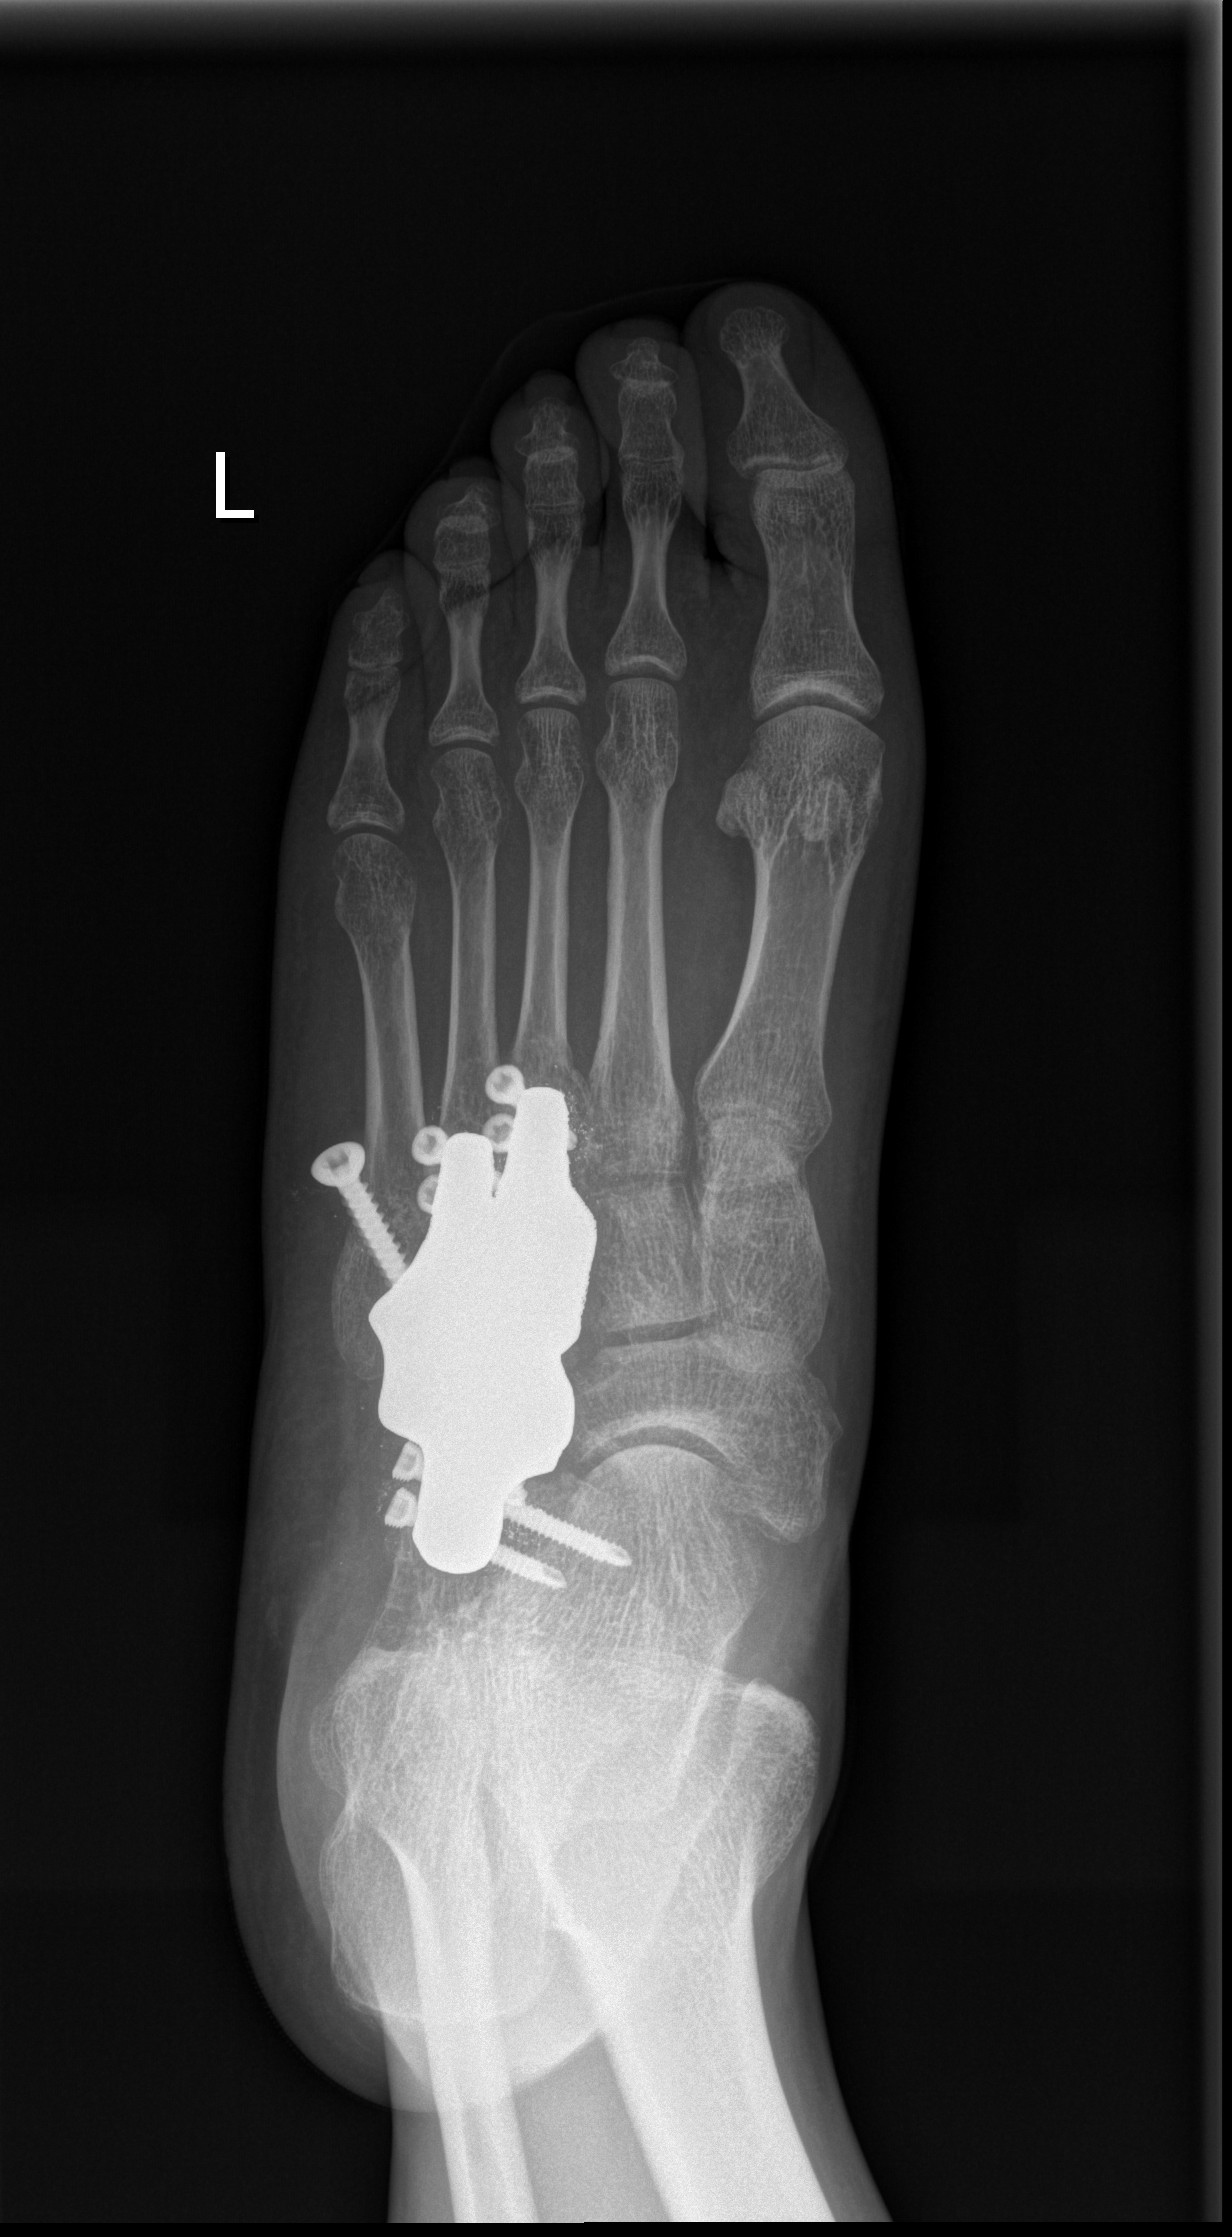

中足骨缺损 价格:

产品特性: 生物惰性钽金属:零排异,安全植入;梯度仿生多孔,微孔促骨长入与血管化,远期实现生物固定;精准解剖匹配,CT建模定制舟骨/楔骨形态,贴合足弓曲度;力学三重优化:弹性模量近松质骨+表面耐磨处理+抗疲劳承重设计

适用症:创伤性中足大段骨缺损(如Lisfranc损伤后);足舟骨坏死/塌陷重建;骨肿瘤切除后结构性支撑;感染清创或翻修术骨缺损修复